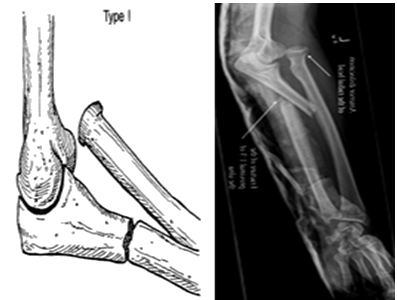

孟氏(Monteggia)骨折:尺骨上1/3骨干骨折合并橈骨小頭脫位